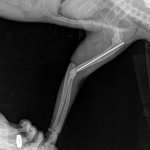

• рентген печени или в отдельных случаях биопсия.